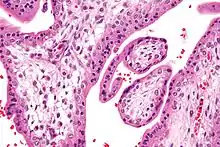

Hofbauer cells are oval eosinophilic histiocytes[1] with granules and vacuoles found in the placenta, which are of mesenchymal origin, in mesoderm of the chorionic villus, particularly numerous in early pregnancy.

Under histology sections, Hofbauer cells have appeared with discernible amount of cytoplasm.